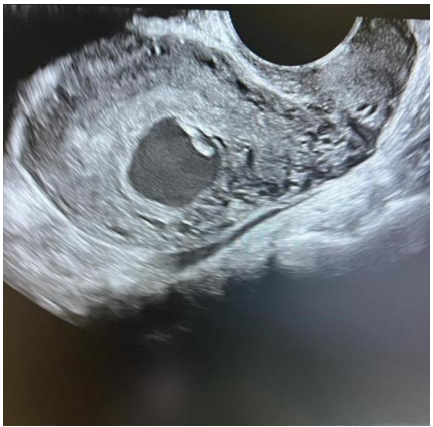

A 16-year-old lady, para 0+2 presented to the emergency department complaining of active vaginal bleeding after medical treatment of missed miscarriage. She had history of two recurrent miscarriages treated by surgical evacuation. Her pregnancy was spontaneous. Her medical history was unremarkable. Clinically she was vitally stable, soft abdomen, no tenderness no palpable masses. Speculum examination was suggestive of normal-looking cervix with bleeding from the os, uniformly enlarged 8 weeks size uterus freely mobile, no cervical movement tenderness, and no adnexal masses. An ultrasound demonstrated a gestational sac about 2.2 cm in diameter. It showed also a yolk sac and a fetal pole of 8 mm without cardiac cavity. Surgical suction and evacuation was performed under ultrasound guidance.  During the evacuation, the gestational sac was noted to be below the suction tube, the procedure was aborted. The intrauterine products were sent for histology which showed fragments of endometrium, blood clots and fibrosed chorionic villi, no evidence of malignancy. Upon reassessment, she was still complaining of the vaginal bleeding. Beta human chorionic gonadotropin was 1450. A Trans abdominal & trans vaginal ultrasound scan showed empty cavity with thick endometrium, a gestational sac below the line of endometrium with a yolk sac and fetal pole without cardiac activity, embedded in the myometrium (Fig.1&2&3&4) .The use of 3-D ultrasound helped in confirming the diagnosis of intramyometrial pregnancy, providing highly informative and detailed imaging to support accurate clinical assessment (Fig.5&6). In view of her parity and future fertility medical treatment was discussed with and accepted by the patient. Methotrexate was administered with a single dose of 50mg given intramuscularly on day 7, the drop was less than 15%. The patient received a second dose of methotrexate .The patient was displaced due to war circumstances. She then continued to have serial pregnancy tests, not able to have quantitative B-HCG test. Her pregnancy test became negative eventually then her menstrual cycle resumed back with regular intervals.

FIG.2

FIG.3

Figure 2

Figure 3